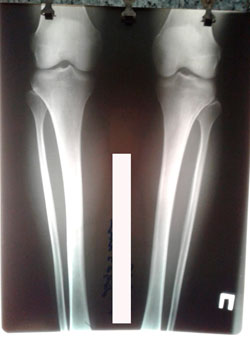

Исходник - 38 лет.

Дата операции 23.03.2020

image-01-04-20-11-29-5.jpg

image-01-04-20-11-29-3.jpg